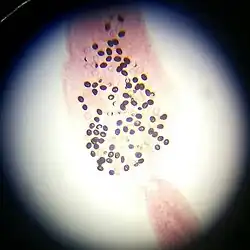

Larven van Trichinella nativa in spierweefsel -

Eieren